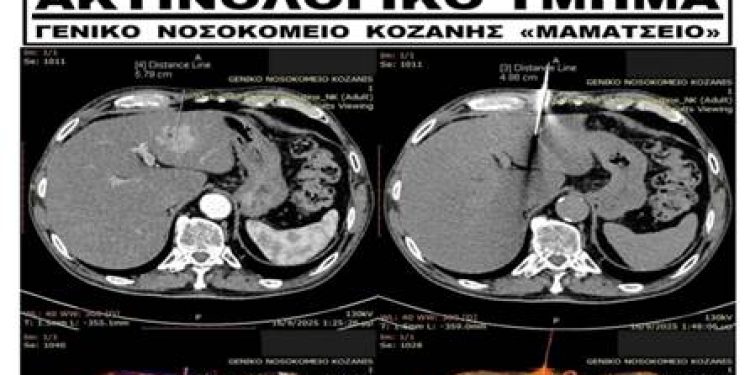

Στο Ακτινολογικό Τμήμα του Γ.Ν. Κοζάνης “Μαμάτσειο” πραγματοποιήθηκε Ολοκληρωτική Διαγνωστική Προσέγγιση Ασθενούς με CT – Καθοδηγούμενη Βιοψία Ήπατος.

Το Γενικό Νοσοκομείο Κοζάνης πρωτοπορεί και πάλι, καθότι είναι από τα ελάχιστα επαρχιακά Νοσοκομεία που διαθέτει προσωπικό με τέτοια επιστημονική κατάρτιση ώστε να εκτελούνται αυτού του είδους οι επεμβατικές μέθοδοι.